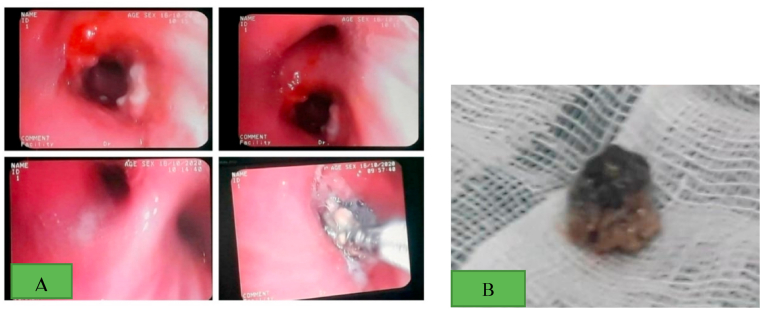

After 5 days, the patient's general condition improved and he was discharged to his own personal satisfaction. However, he was referred to our hospital 24 hours later due to the persistence of his cough and SOB. He was admitted under the supervision of a pulmonologist, and HRCT and RT-PCR were ordered. The result of the lung HRCT showed mosaic attenuation in the right middle and lower lobes due to air trapping (Fig. 1). In addition, the RT-PCR for COVID-19 was negative. Moreover, the results of the chest X-ray (CXR) revealed a round opacity in the right main bronchus (Fig. 2). Clinical suspicion was placed on the FBA based on the radiologist's comment (Fig. 1, Fig. 2). Rigid bronchoscopy was performed to further investigate and diagnose the patient, and an olive kernel was discovered in the right main bronchus (Fig. 3 A, B).

Fig. 3.

The rigid bronchoscopy view of the aspirated olive kernel (A), removal of the olive kernel (B).